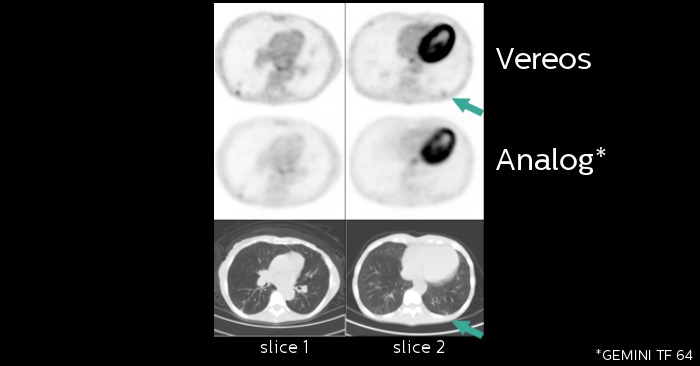

Sample images acquired in a clinical study of the Vereos PET/CT system at The Ohio State University. Investigational device limited by law to investigational use.